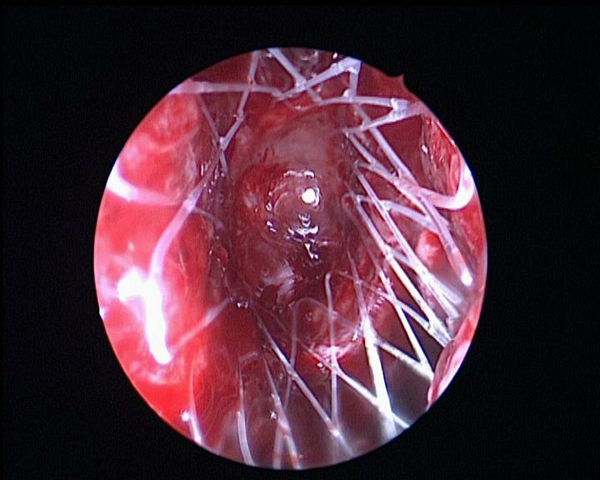

在鼻内镜的引导下,随着一个白色网状物在额窦口缓缓撑开,西北地区首例降解鼻窦药物支架在我耳鼻咽喉头颈外科病院石季副教授指导下,由副主任孙斌医师的操作下顺利植入,使鼻内镜下鼻窦手术的微创化、便捷化治疗进入一个新阶段。

降解鼻窦药物支架可以在术后有效的撑开鼻窦口,保持窦口通畅,该支架还可持续释放抗炎药物,减轻了局部粘膜水肿,术后一个月完全降解,无需再次手术取出,既减轻了患者的痛苦,又节约了复查换药时间,提高了患者的依从性,术后复发导致二次手术的概率大大降低。